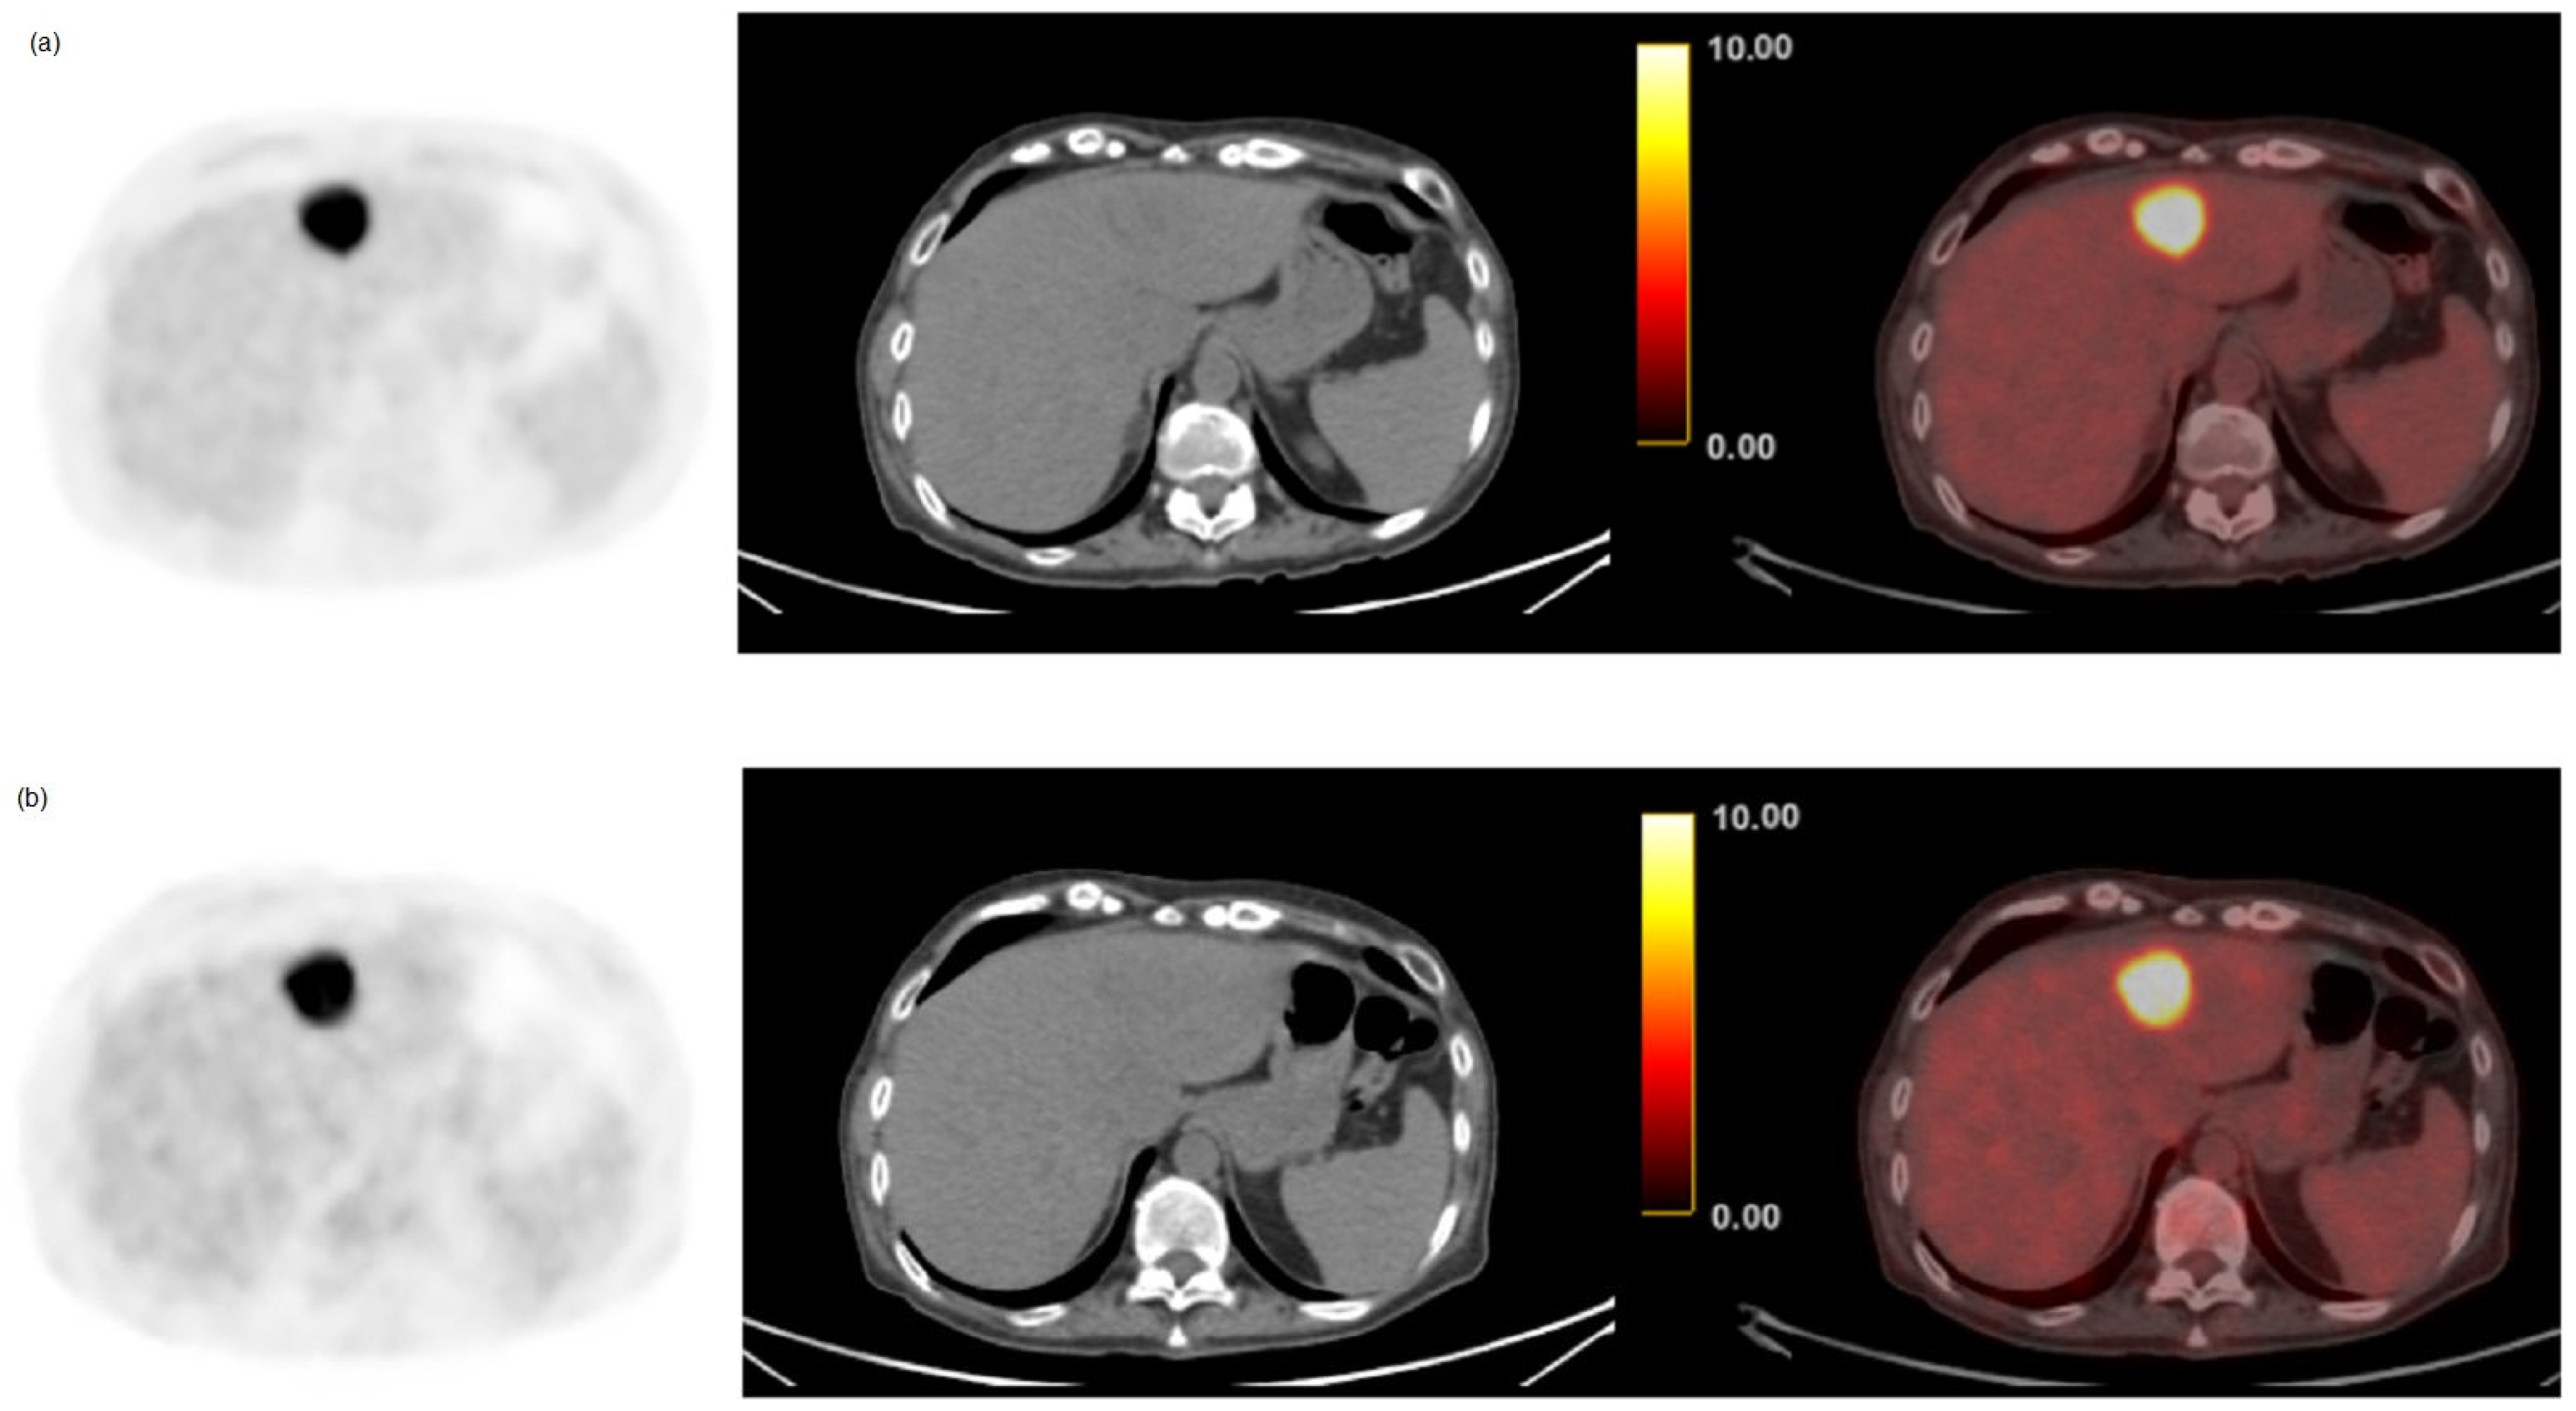

3.3. Semi-Quantitative and Per-Lesion Analysis

4. Discussion